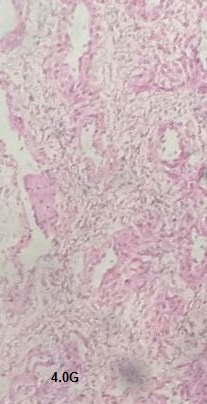

Nasal histopathology was carried out to determine the possible toxic effects of the developed formulation on the surface of the nasal mucosa. Fig. 10 represents five different representative images of sections of nasal mucosa viz., (A) positive control treated, (B) negative control treated, (C) mucosa treated with G5PPID, (D) nasal mucosa treated with G4PPID and (E) nasal mucosa treated with pure donepezil. In the negative control group, nasal mucosa was found to be extensively damaged on the epithelial surface and an internal tissue treated with isopropyl alcohol. The positive control was treated with PBS pH 6.4 and was found to be intact with preserved structure. In the nasal mucosal sections treated with G4PPID and G5PPID, neither structural damage nor cell necrosis was represented and stabilized their biocompatibility. These observations were following the pH value of G4PPID and G5PPID (5.87±0.11) which was within the pH range of human nasal mucosa (5–6.5) indicating its safety for nasal administration [23].

A

B

C

D

E

Fig. 10: Photomicrograph of sections of goat nasal mucosa of (A) positive control group, (B) negative control (C) G5PPID (D) G4PPID and (E) pure donepezil treated (magnification: 400X)